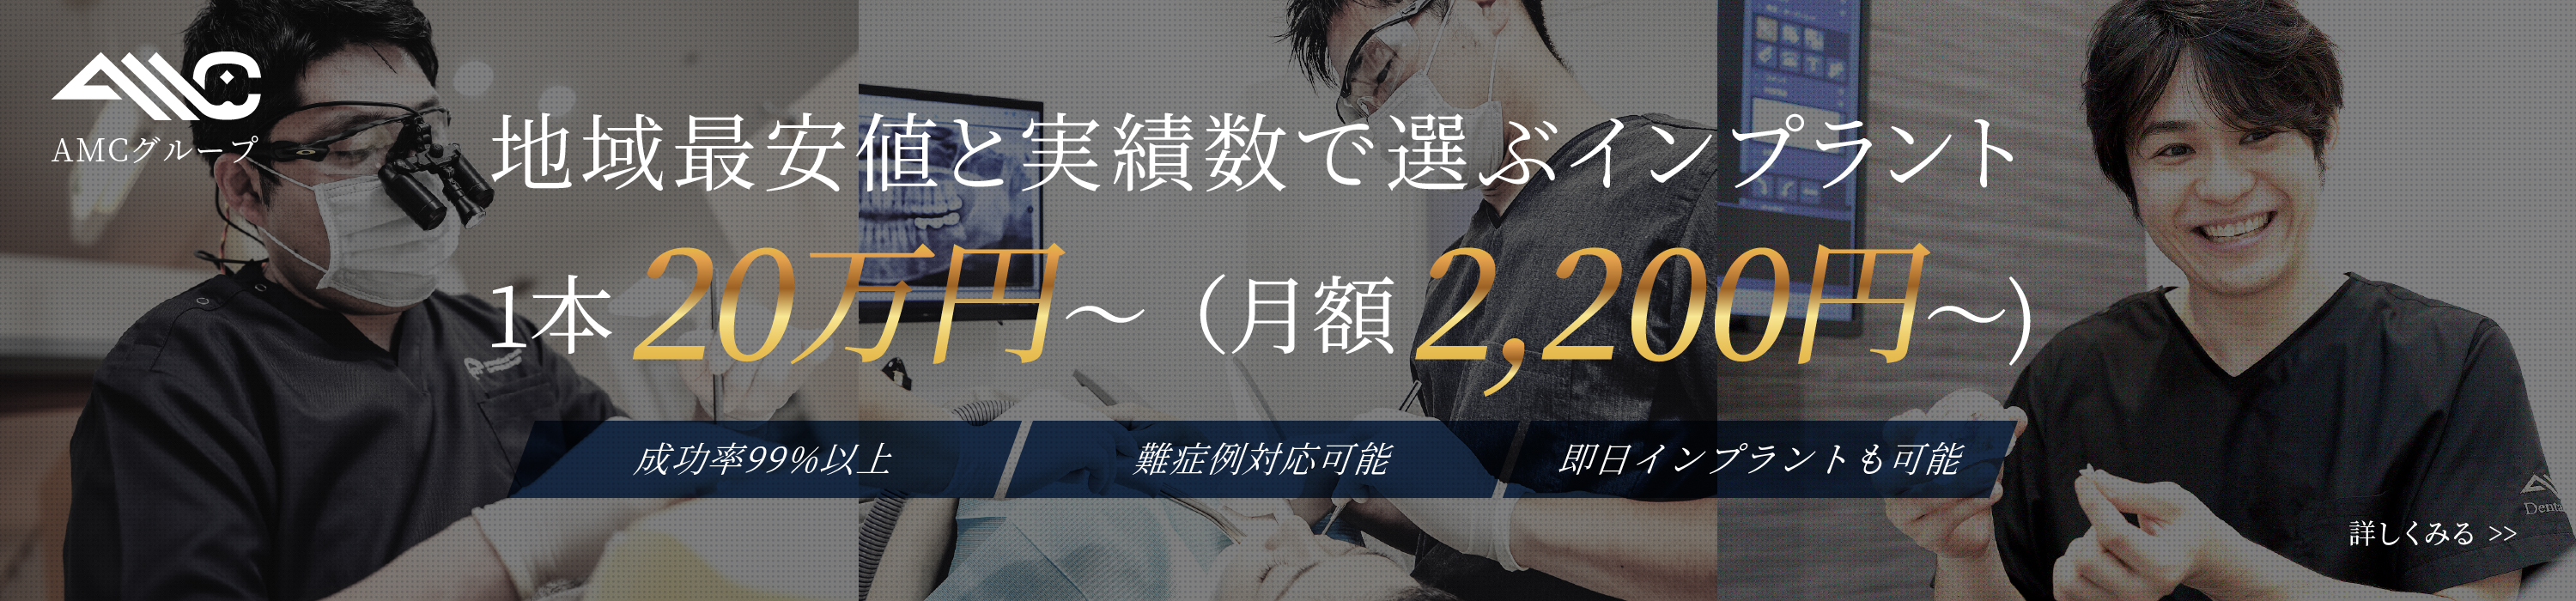

インプラント

インプラント治療について

インプラント治療とは

インプラント治療とは、歯を失った箇所に人工の歯根(インプラント)を埋入し、歯を補う治療法です。

当院のインプラント治療は、お口全体のバランスを考慮して行います。CT画像で精密に診査・診断を行い、かみ合わせのバランスを綿密にシミュレーションします。顎骨の幅や高さには個人差があり、状態によって、そのままではインプラントの埋入が難しい場合もあります。そのような場合には外科手術で骨量を増やしてからインプラントの埋入を行うので、骨の量が不足している方でも手術が可能です。